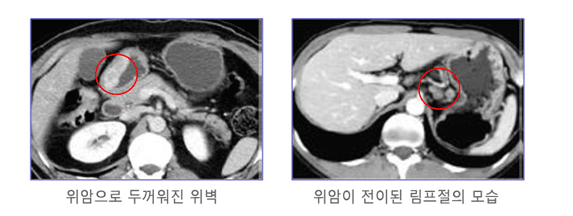

위암은 위안에 악성 종양이 생기는 것을 말하고요. 위암은 세포의 비정상적인 성장과 분열로 인해 발생 해요. 위암은 예사로 위의 상부에 위치하고 있는 점막세포에서 시작되며, 그 다음에는 근육층과 지방층까지 퍼져나갈 수 있어요.

위암은 흔하게 소화기관의 다른 부분에 나타나는 암보다 적게 진단된다 하였습니다. 그렇지만 위암은 초기에는 대다수 증상이 없어서 발견이 곤란한 경우가 대부분입니다 따라서, 위암은 진행되면서 증상이 심해져서야 탐지되는 경우가 많이 들어있다고해요. 그리하여 위암 검진을 꾸준하게 받아서 확인하는게 중요하고요.